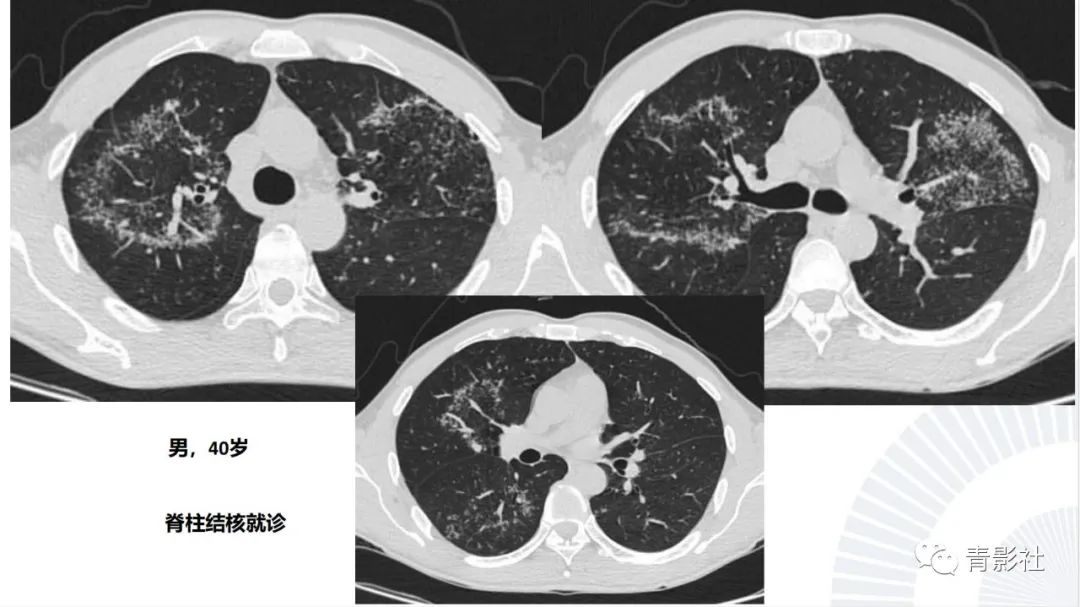

【PPT】肺部反晕征影像诊断思维-6